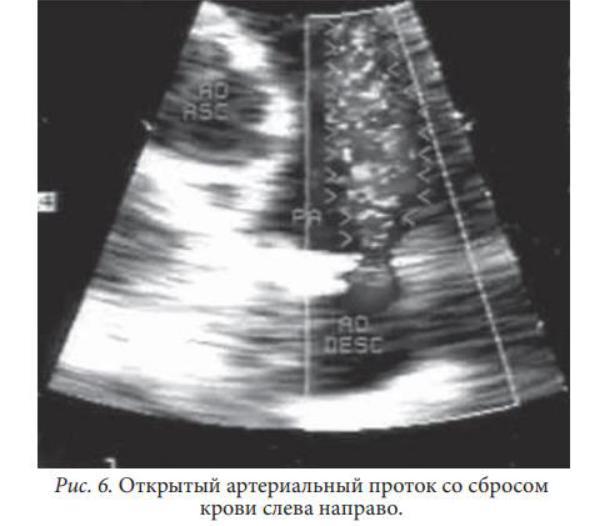

Открытый артериальный проток визуализируется в виде дополнительного сосуда, соединяющего нисходящую аорту с бифуркацией легочной артерии

Поток крови направлен из аорты в легочную артерию